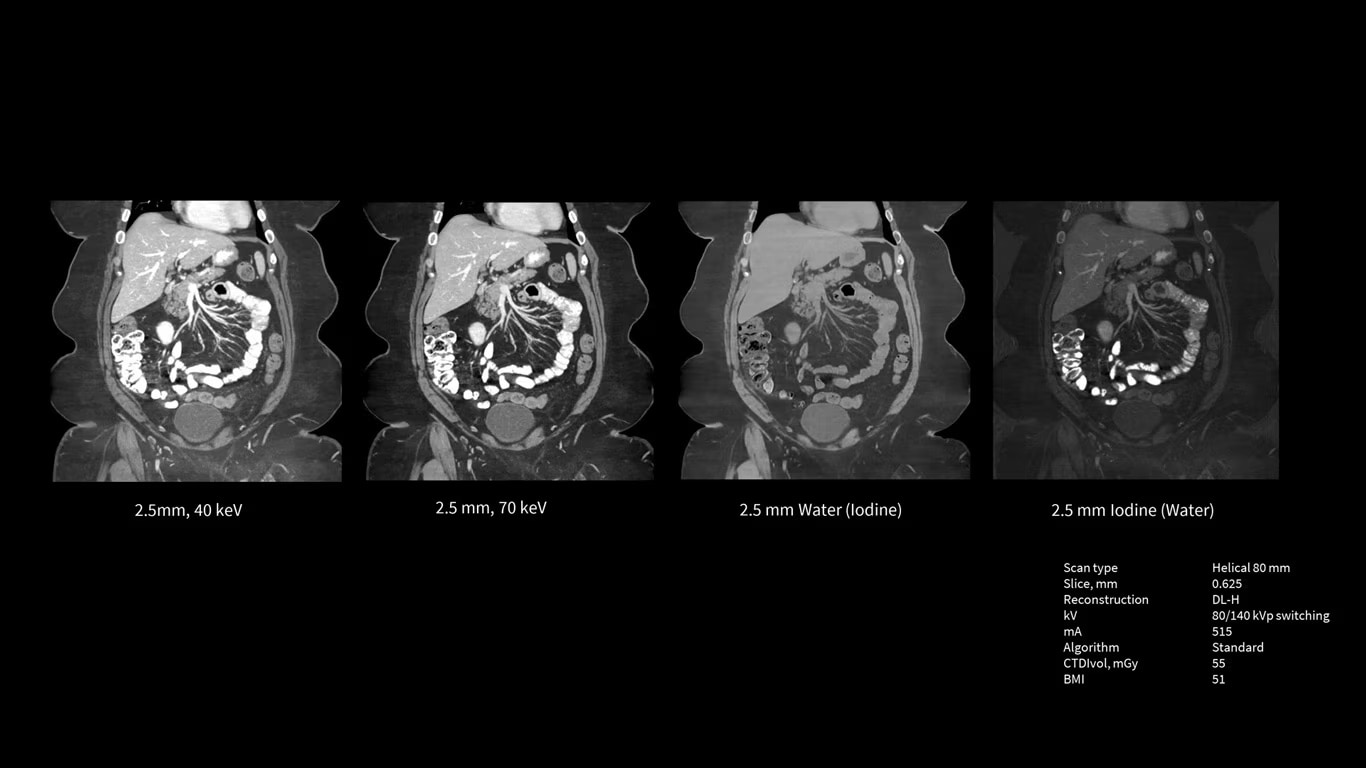

The Revolution Apex Platform was built with exceptional technologies throughout the imaging chain and with an Effortless Workflow model of efficiency to help you meet your imaging challenges. To meet tomorrow’s needs, we’ve built it with scalable detectors that allow you to take your practice to the next level at any time. The Revolution Apex platform is the powerful, adaptable technology you need to lead CT now and into the future.

Scalable Clarity Detector

The Revolution Apex platform has a modular design that allows for hardware scalability. You can start with Revolution Apex Select with a 40mm detector and in the future, when you need to grow your service line, you can scale the detector up to 160mm.